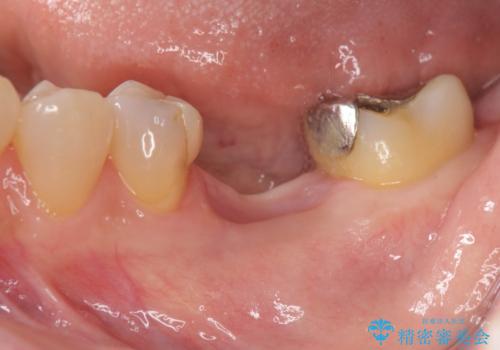

抜歯後の補綴 セラミックブリッジ治療

- 他院で行われた抜歯後の機能回復について相談に来院されました。

インプラント治療、入れ歯と比較し、前後の銀歯や詰め物の問題も一緒に治療のできるブリッジ治療を選択されました。